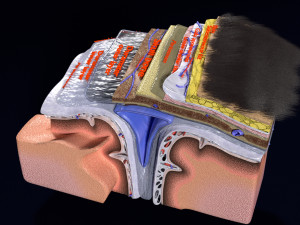

A blend model of brain along with its covering layers (meninges), skull bone and scalp labelled in detail and anatomically precise. The parts depicted are white, gray, pia, arachnoid, dura, bone, skin, fat, aponeurosis, periosteum, falx cerebri and more.

The material is high resolution image textures and normal maps based on non overlapping UVs. The texture and normal maps are packed with the blend file itself.